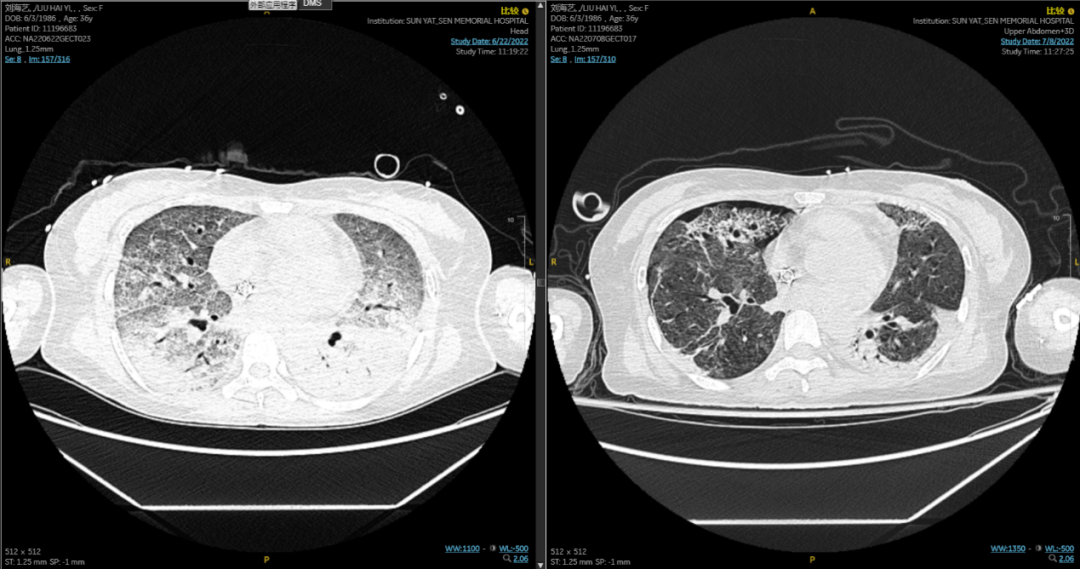

患者ECMO辅助前后胸部CT对比

V-V ECMO建立后,患者氧合得到迅速改善,各项生命体征平稳。目前,该患者恢复良好,已在ECMO辅助17天后,成功脱离ECMO支持。